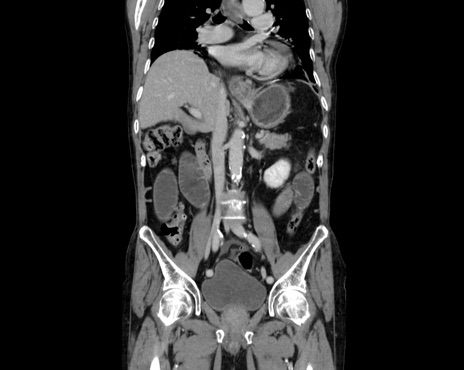

症例26(冠状断像)

【症例】80歳代男性

【主訴】嘔吐

【現病歴】昨晩2回嘔吐あり、今朝になっても嘔吐あり。来院。

【既往歴】胃潰瘍

【身体所見】意識清明、BT 37.6℃、BP 166/95mmHg、HR 100bpm、SpO2 97%、腹部:平坦・軟、腸蠕動音聴取良好、圧痛なし。

【データ】WBC 21900、CRP 1.4